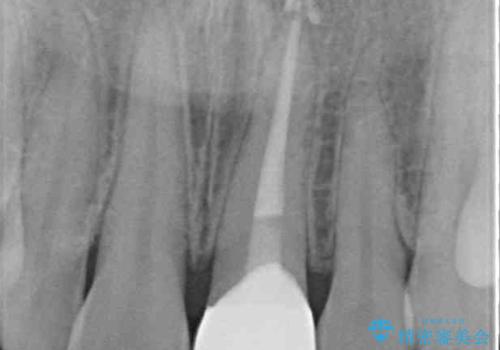

- 転んだ際に欠けてしまった前歯の変色が気になるとのことで来院された患者様です。

診察やレントゲン写真より神経組織の失活が認められたため、根管治療、ファイバーコアによる土台築製後、オールセラミッククラウンにて補綴することとしました。